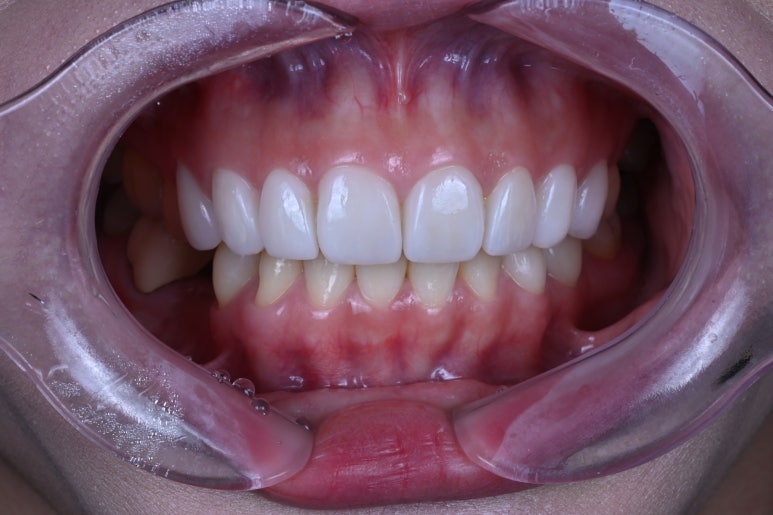

아래 치아와 비교해보시면 더욱 더 뚜렷한 색상차이를 확인하실 수 있죠.

입안에 위치하고, 눈코입과 함께 보면 요 색상이 꽤나 자연스러움을 아실 수 있으실겁니다.

윗니와 아래이가 같이 있을 때 가장 도드라집니다.

치아의 가로-세로 비율이 좋아졌고, 좌우 대칭이 상당히 좋아졌습니다.

얼굴형과 어울리는 치아의 모양을 갖게되셔서, 참 결과가 좋았던 기억..^^